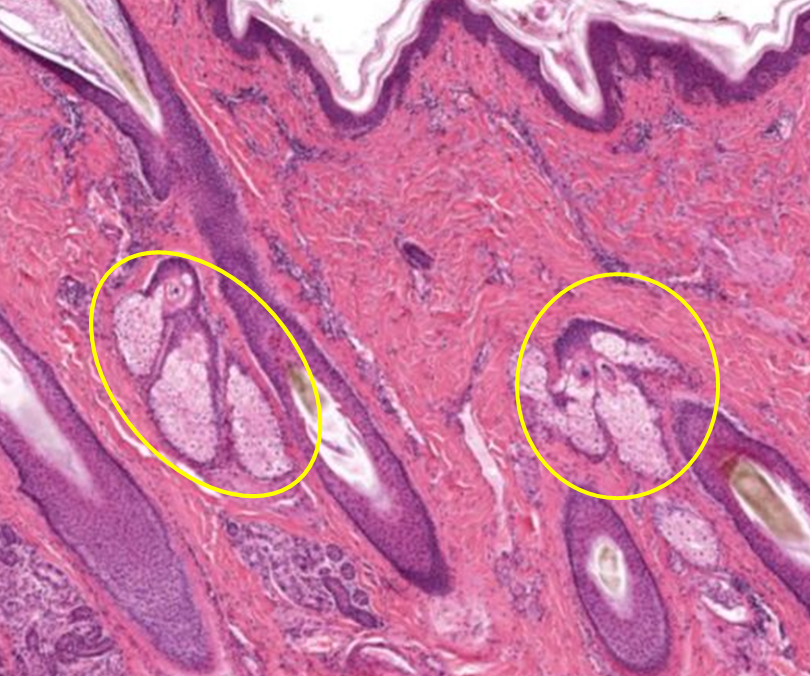

Glândula sebácea